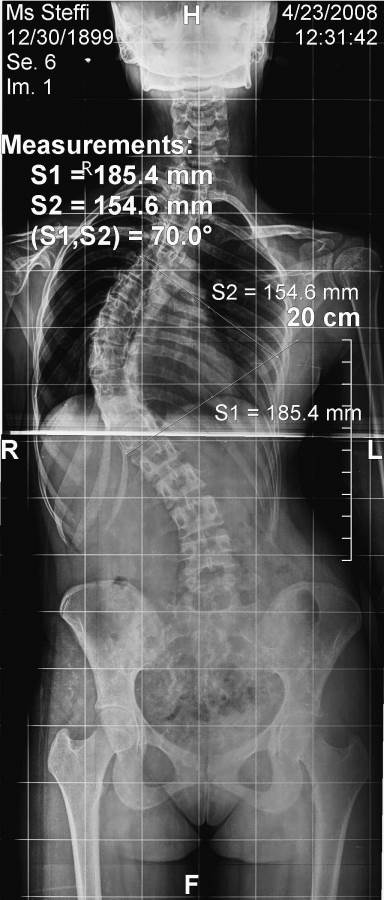

Pre-Operation

Scoliosis